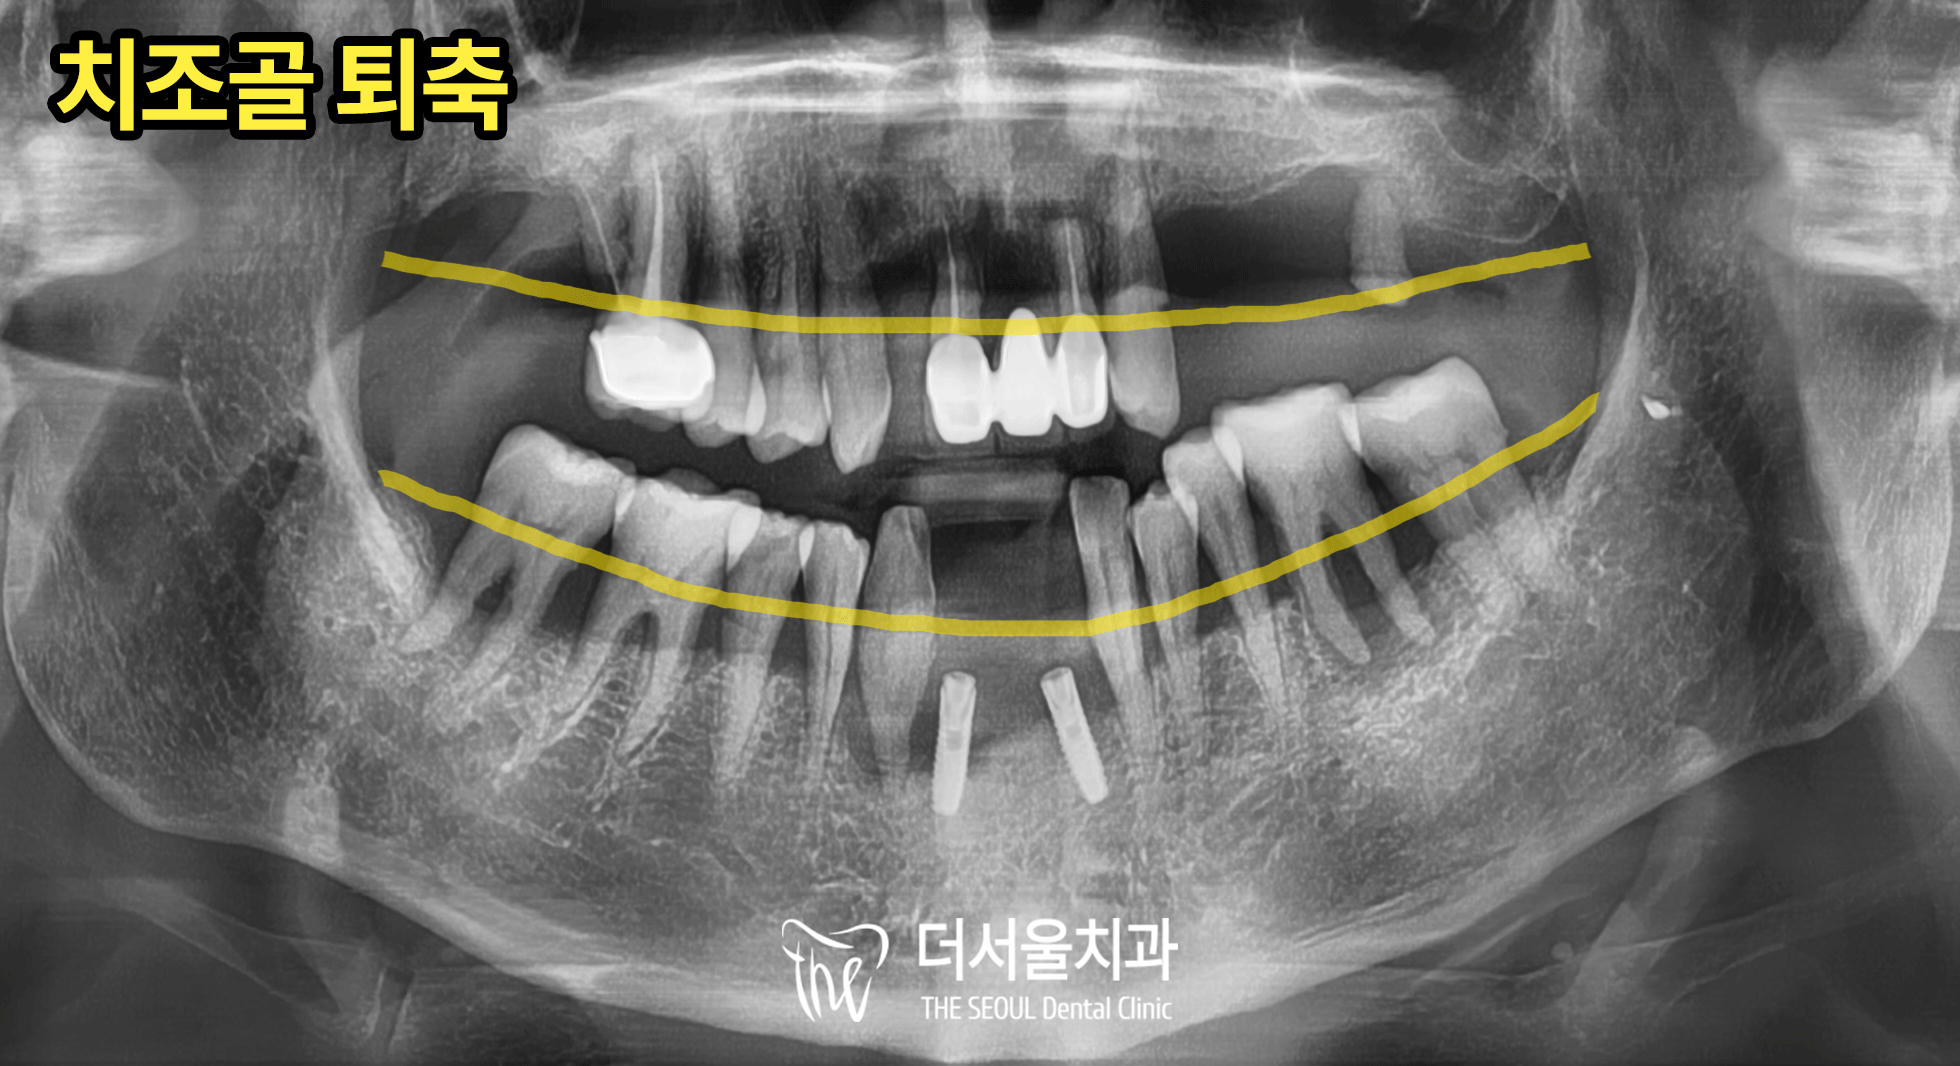

전반적으로 치조골 퇴축(Bone loss)이

다수 진행된 모습과 함께

과거에 식립되었던 픽스처 주위로

심한 염증을 확인했습니다.

특히 사진 기준 왼편 픽스처 주변의 염증은

옆의 측절치(#42) 뿌리까지 번져

픽스처와 42번 모두 발치가 불가피한 상황입니다.

아래턱 대구치는

맞닿는 대합치 없이 오랜 시간이 지나

정출되어 있습니다.

잇몸뼈가 많이 퇴축되어있고

치근단 주변으로 염증이 번졌기 때문에

보존치료의 예후가 좋지 않을 것으로 판단됩니다.